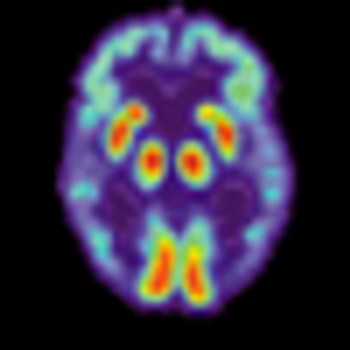

A study presented by Canadian investigators at the 24th Congress of the European College of Neuropsychopharmacology (ECNP) in Paris, September 5 evaluated whether methylene blue can reduce residual symptoms of depression and mania in bipolar disorder.